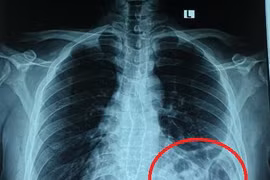

(Vietnamdaily) - Nam thanh niên một tháng trở lại đây liên tục ho và đau tức ngực nhưng chủ quan nghĩ hậu COVID19, không đi khám. Đến khi vào viện tình trạng đã nặng, đại tràng, dạ dày "chui" lên ngực trái.